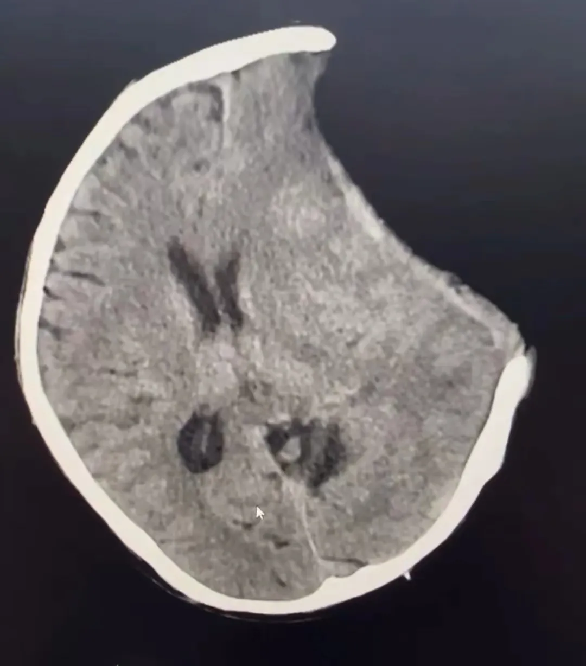

术后: